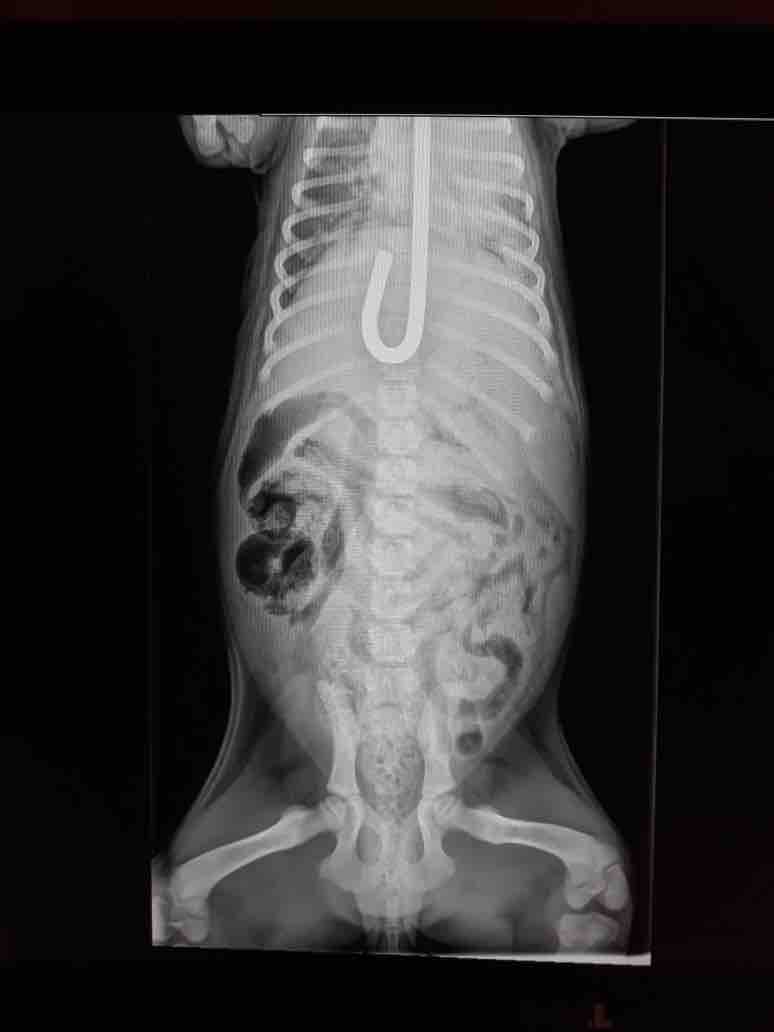

Yesterday morning a vet tech from Tampa called my cell phone and was desperately trying to find help for a young puppy who had impaled herself on a metal rod that went into her mouth down her throat and into her stomach. She had surgery to remove the rod however she has developed additional problems and needs emergency surgery. Canela has Intussusception is when a part of the intestine telescopes or folds in on itself. Estimate is $7000-$9000. I am going to have to close intake while we try to raise funds for the poor puppy. Canela needs your help and prayers.